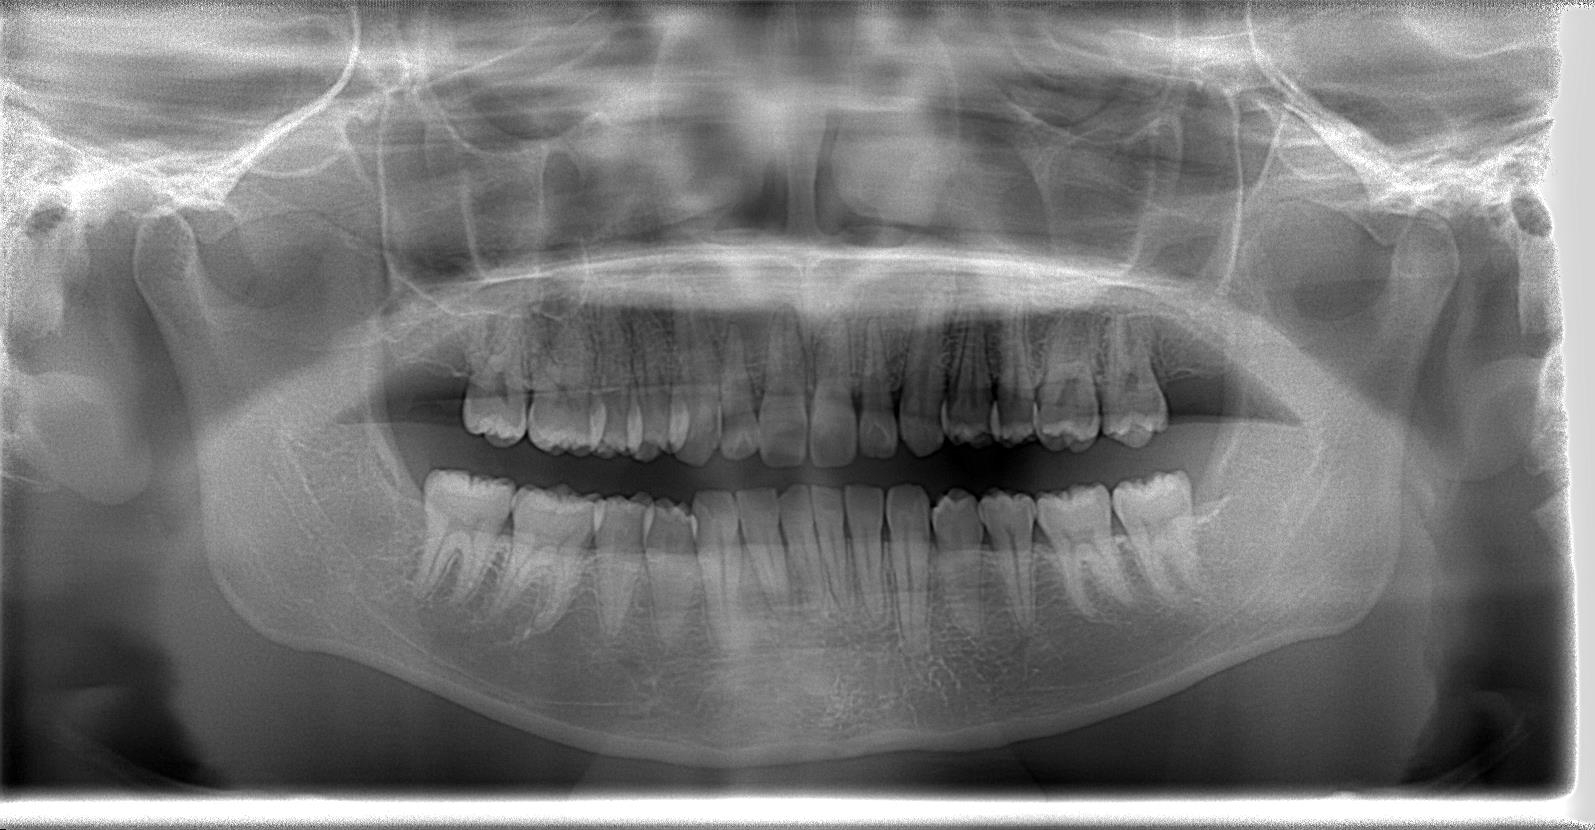

[術前パノラマレントゲン写真]

第3大臼歯を抜歯して矯正配列している症例です。

[治療後のパノラマレントゲン写真]